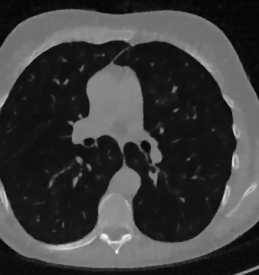

As real patient images, we have downloaded the widely used AAPM Low Dose CT Grand Challenge data set by the Mayo Clinic [35]. The considered images are 512×512512512512\times 512 pixel reconstructions of human abdomen, computed from full-dose acquisitions. In Figure 2 we depict one image with two zooms-in highlighting areas with different anatomical structures, such as pulmonary details, sections of ribs and low-contrast inter-costal muscles. In all the experiments reported in 5.1, we have used the images from the data set as ground truth xGTsubscript𝑥𝐺𝑇x_{GT} references. Coherently, we simulate the tomographic projections of the ground truth images, according to a 2D fan-beam geometry, and we add to the sinograms white Gaussian noise with 102superscript10210^{-2} noise level. To address sparse-view CT reconstructions, we considered two different protocols: the first one is a full angular acquisition with 1-degree spaced projections (we call it P360,360subscript𝑃360360P_{360,360} in the following); in the second one the scanning trajectory covers 180180180 degrees and computed only 606060 projections (it is labelled as P180,60subscript𝑃18060P_{180,60}).

Refer to caption

Figure 2: A ground-truth image from the Low Dose Mayo data set, with two zoomed crops on regions with different anatomical structures.